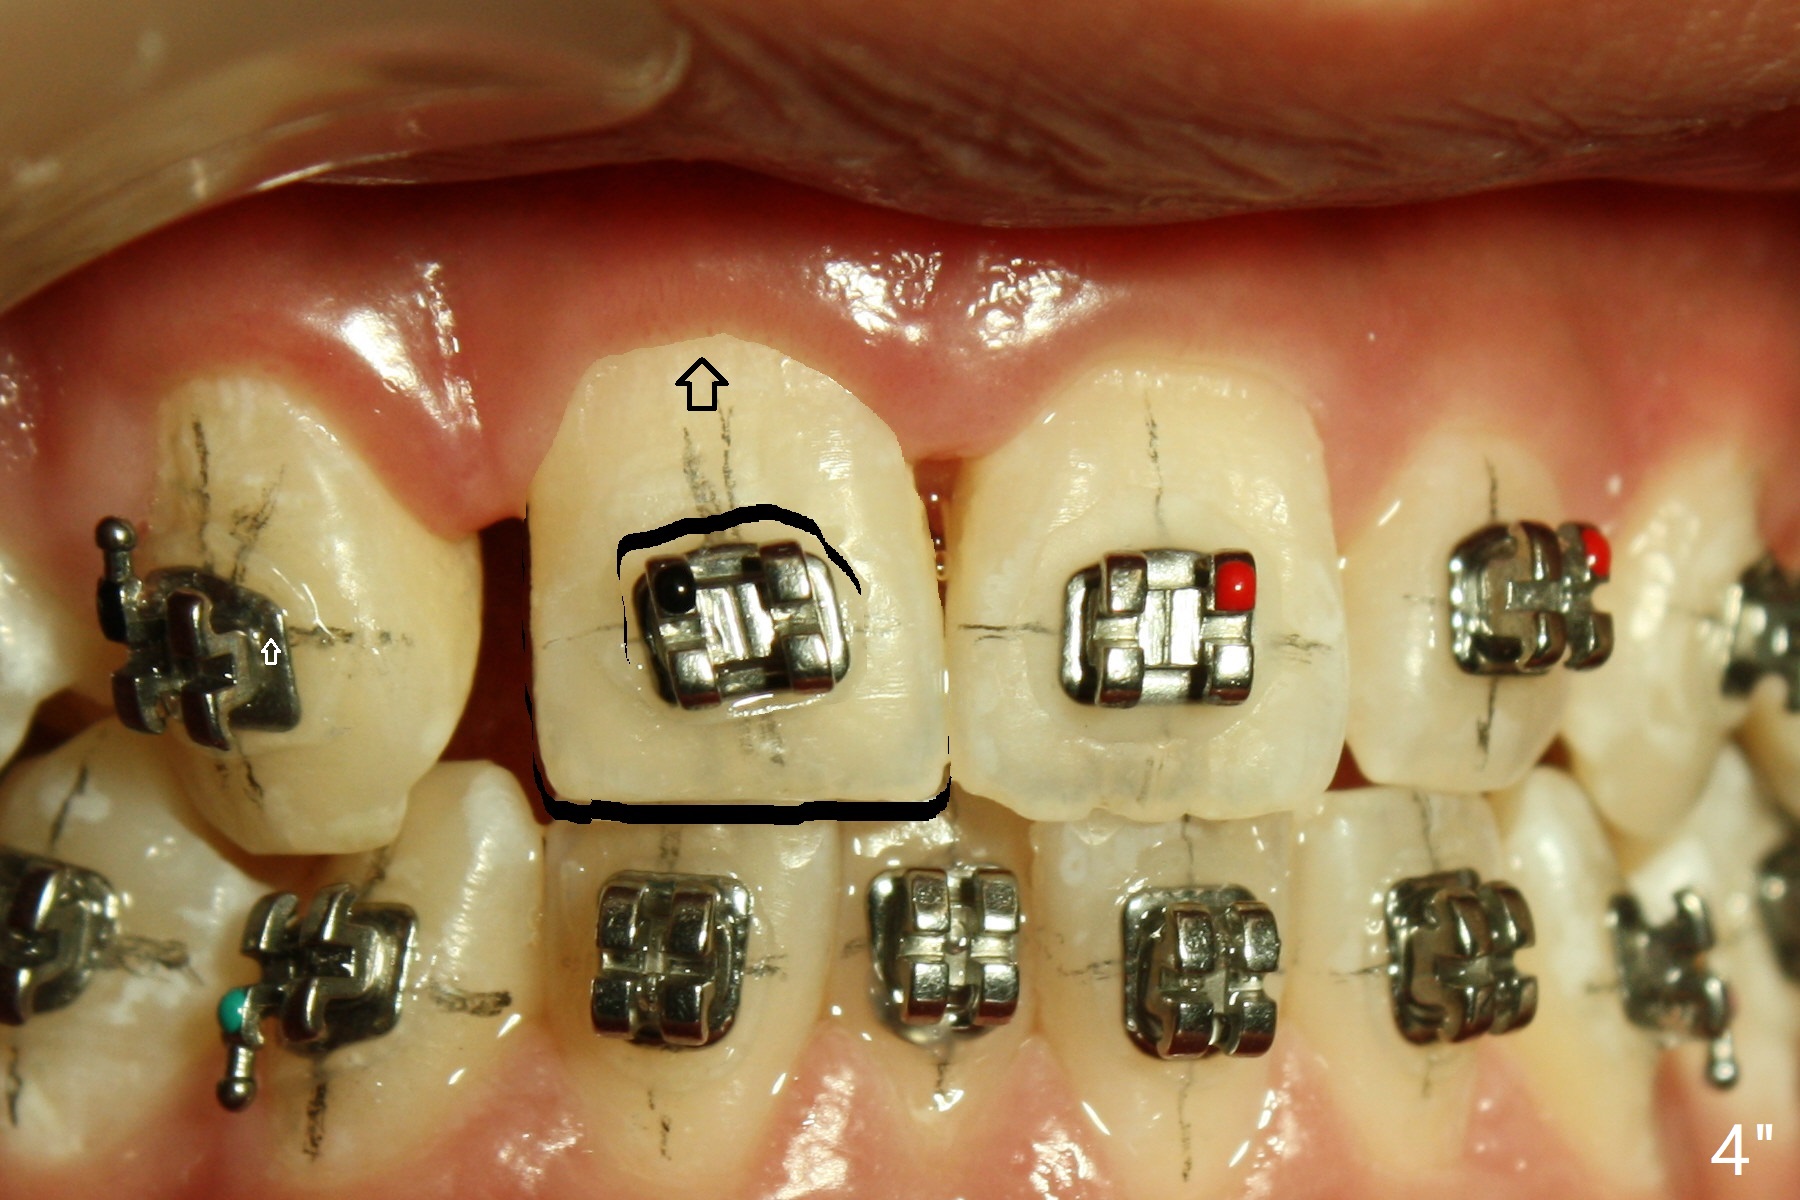

A 15-year-old man finishes orthodontic treatment for congenital missing lateral in 13 months. Molar Class I relationship remains the same (Fig.1,2,4,5). The upper diastemata mesial to 4s (Fig.4,7") close with correction of the upper midline deviation (Fig.2'-4'). The kid is unpleased with the elongated UR1 (Fig.2',3'). In fact it is a preexisting condition (Fig.2 arrow, 2"), but bracket placement at UR1 should have been overcorrected (incisal placement, Fig.3"). The intrusion should be done (Fig.4") before closure of the diastemata, since anchorage may be weakened when the separation between UR1 and 3 increases by using open coil spring. To prevent immediate relapse of the diastema between the upper central incisors, a fixed retainer is placed lingual before debracketing (Fig.6,6',6").